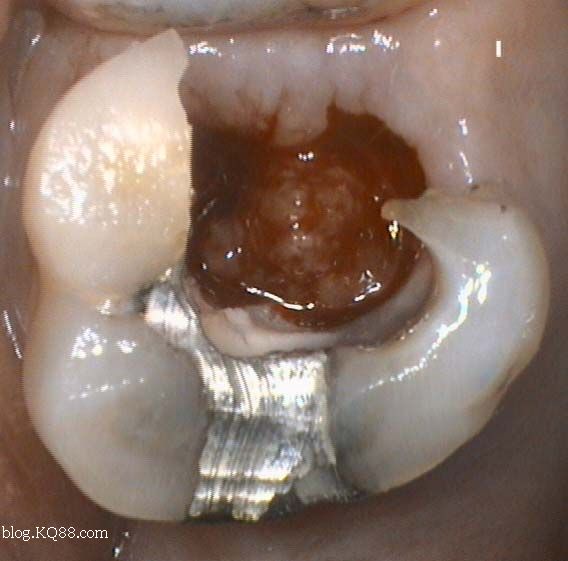

如何判斷牙齒牙洞已經(jīng)深入到牙髓?,牙齒牙洞深度判斷,如何確定已影響牙髓?

2、探診檢查:使用牙科探針檢查牙洞周圍組織的健康狀況,了解牙洞深度及與牙髓的關系。